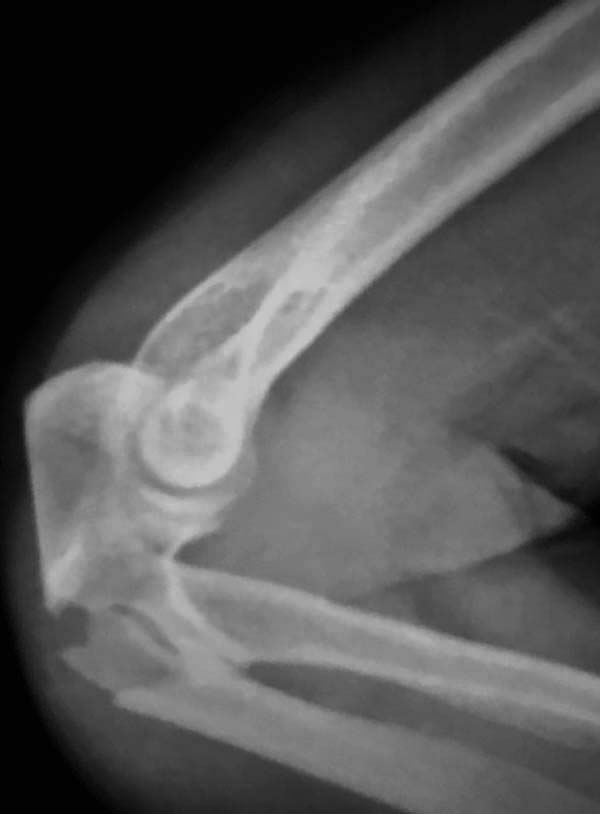

фиксация, даже специальной пластиной, может осложнится. Протез головки

после удаления предупреждает нестабильность в суставе и деформацию оси

конечности в будущем!